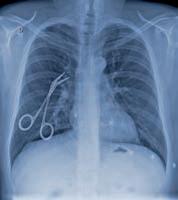

Ejemplos de mala praxis

 Instrumentos de cirugía que han quedado en el interior del paciente una vez terminada la operación.